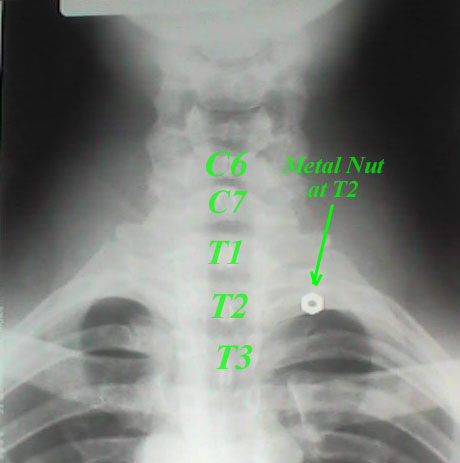

Next, I took an x-ray with me in a neutral position, such as seen above. However, the film taken was an AP, not a PA, with my back...and the nut...to the side of the film. In the photo above, I am facing the film 'bucky' for the purpose of the photograph. Additional photos show my positioning during other portions of the experiment. See below:

The Neutral AP X-ray

I had the camera remote in my hand, which allowed me to take the picture just before and after the x-ray was exposed. The light is turned off to assure proper alignment during the x-ray taking procedure. See the AP film positioning below and the resultant film.

As you can see, the metal nut was precisely at the T2 vertebral level. "Ah-ha", you say? Just wait. I am not in the same position that Kennedy was in. He had his right arm elevated, as it was resting on the car's side, right? I wonder if that little nut would move if I put myself in the same position. Well, let's see. Below you'll find the positioning and x-ray of me with my arm in a similar position.